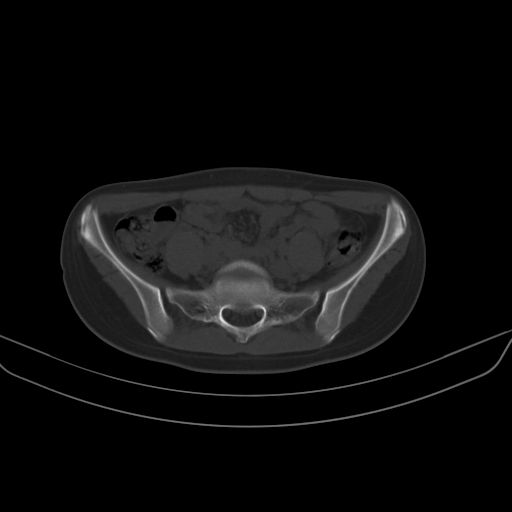

以下是引用子十在2008-7-11 21:12:00的发言:[br]考虑强脊

以下是引用zsl6918在2008-7-11 21:40:00的发言:[br]双侧骶髂关节骨质破坏以下三分之一为主,符合强直性脊柱炎表现

以下是引用zhangzhongshou在2008-7-11 21:41:00的发言:[br]患者是女性,hla-b27抗原(—),首先不太考虑强直性脊柱炎,建议查类风湿因子,骶髂关节改变考虑类风湿性关节炎可能性大,建议进一步检查。